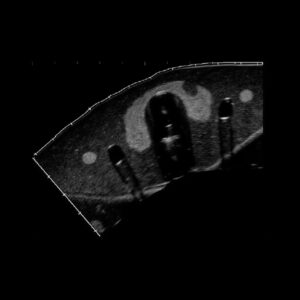

Qualité des images échographiques

Échogénicités des tissus

Nuances moins saturées et plus lumineuses sur les images échographiques. Un rendu très proche de la réalité.